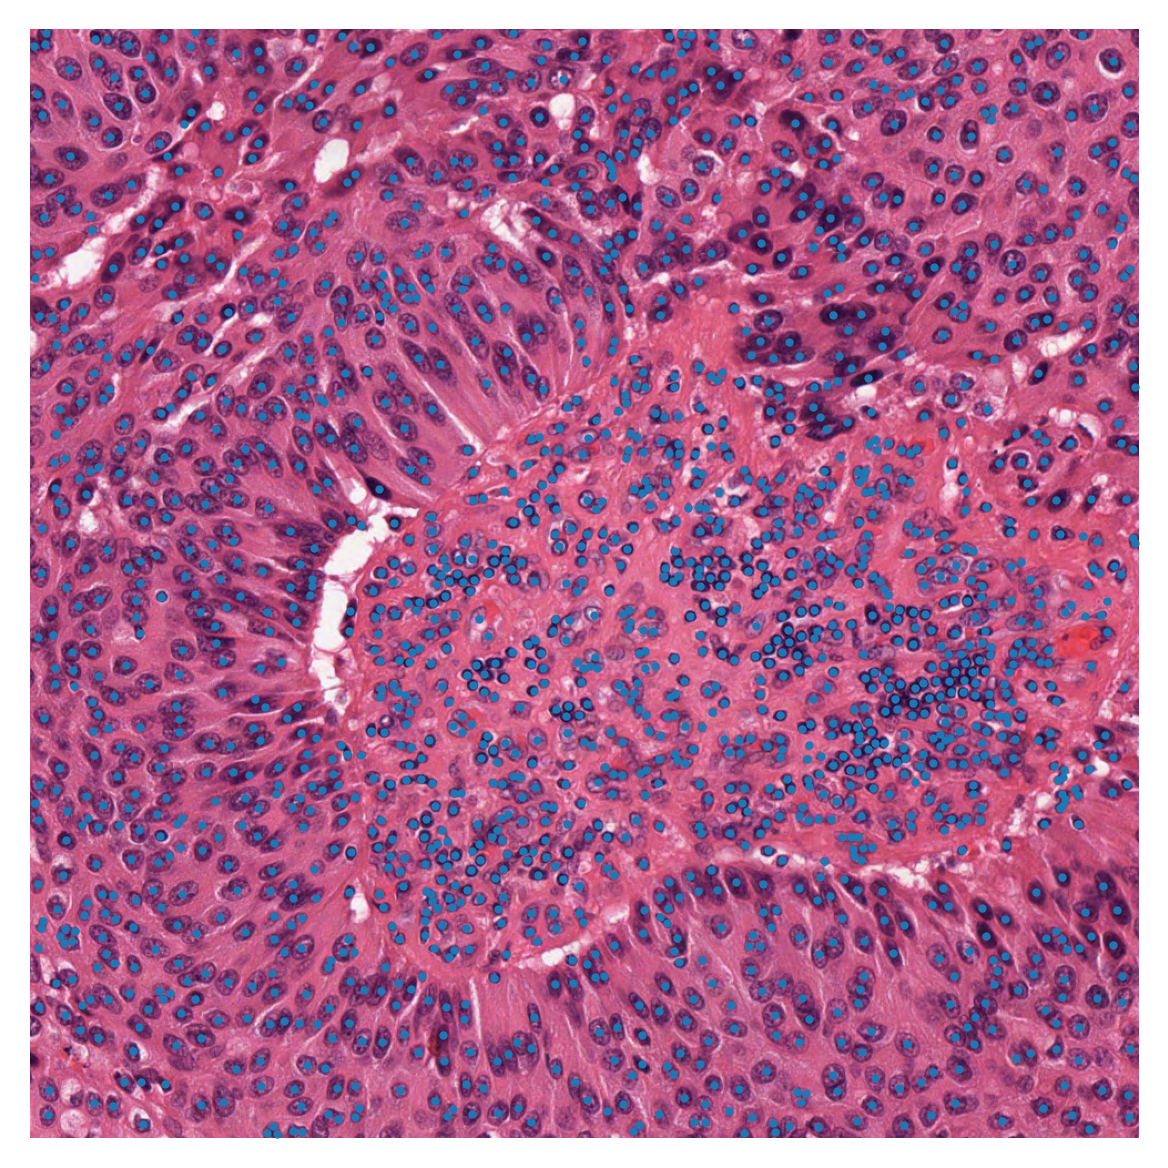

To see better what we are dealing with here, we show the image, first in its original form, and then with the desired centroids overlaid.

../../_images/7325a49b7276616c2d72a16cccc02c1d8d78a8483e59cf01b0c74bd47b64946c.png ../../_images/52d644e59037406b8566712af6a9d9810a6e4592b12593b534d104aad90ee62f.png

Patches based on point annotations

As you can see in the above figure, each nucleus is marked with a blue dot. To train a nucleus classifier computer program (or a beginning pathologist), it is helpful to see a nucleus in context, that is, within a surrounding patch. Therefore, we extract, for each nucleus, a patch centred on that nucleus. If the third column of our dataframe has been completed meaningfully (which is not the case in our example), it is then easy to save patches in different folders based on their biological significance or class=classification. This can be done using functions from the Python classes defined in our module patchextraction . (We are using both class=biological classification and class=Python class for coding.) The patch_extractor yields patches from the image, input_img, based on the centroids_list in a one-by-one manner. In the next code cell, we show how to use the function get_patch_extractor to obtain a suitable patch_extractor